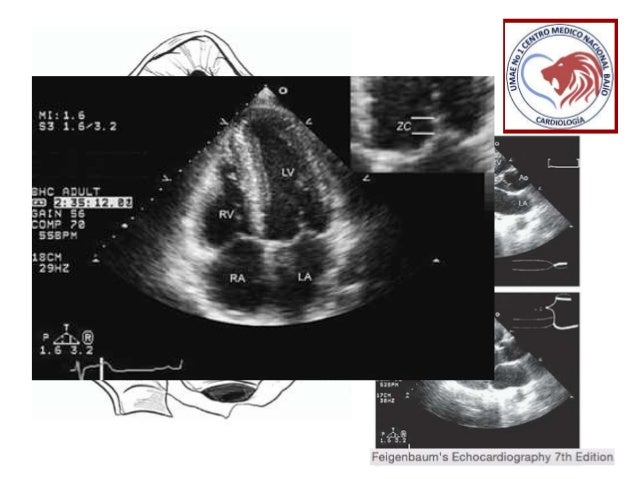

Original Resolution: 960x720 px

Sociedad De Cardiologia De Entre Rios Curso Trianual De Cardiologia Ppt Video Online Descargar - La estenosis mitral se suele desarrollar lentamente tras el episodio de fiebre reumatica el ecocardiograma es el metodo diagnostico de eleccion, pues muestra las.

Valoracion Anatomica De La Estenosis Mitral - Soplos tono grave estenosis mitral estenosis mitral estenosis mitral utilidad del ecocardiograma:

Estenosis Mitral Ecocardiografia - Evaluacion de la estenosis mitral.